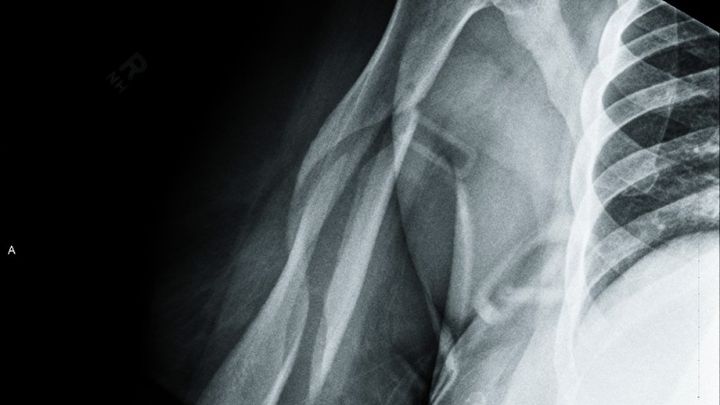

I was taken away in an ambulance to the ER . After many hours of waiting, tests, scans and an Xray, I got the bad news. My right humerous was broken in THREE places. Oh my lord! You can see the break in the X-ray photo. What do I do? Where do I go? I had no insurance. They couldn't put a cast on because of the location and nature of the break. I left the hospital with cut up clothes, stitches above my left eye, a sling and 3 pain pills!

I found a good worker comp lawyer and a real ortho specialist. On March 31st, 2015 ( my 56th birthday) I saw the doctor. The X-ray was taken. He took one look and said I needed surgery. It would never heal on its own. He classified it as a "disastrous break." In May, I had an appointment with another specialist. He only worked on upper extremities. Yup, needs surgery, with a rod and some screws and other things. My surgery was set in September of 2015. I would never have 100% use of my right arm, ever again. He didn't know how much damage the break caused, until he cut my arm open. Then a nurse took my blood pressure. It was sky high, 198/110. The doctor nealy fell over and wondered how I was still standing. Now, I needed BP meds and other tests. The insurance company denied 99% of every request. I failed the pre-op and the surgery was cancelled.